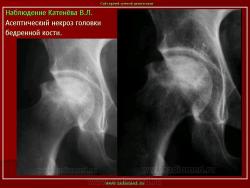

Остеохондропатия головки бедренной кости

(болезнь Легга-Кальве-Пертеса)

Изменения на рентгенограммах зависят от стадии процесса.

В I стадии (асептиче­ского некроза губчатой кости эпифиза и костного мозга) изменения отсутствуют либо незначительные: в виде остеопороза костей, образующих тазобедренный сустав, извилистости и неравномерности хрящевой эпифизарной пластинки, неоднородности и пятнистости шейки бедра, некоторого расширения щели сустава.

Во II стадии (импрессионного перелома) головка бедренной кости утрачивает характерную трабекулярную структуру, шейка бедра становится более остеопоротичной. Суставная щель отчетливо расширяется по сравнению со здоровым тазобедренным суставом. Эпифиз головки уплотняется, склерозируется и деформируется (вследствие сохраняющейся нагрузки).

В III стадии (фрагментации эпифиза) суставная щель по-прежнему расширена, головка сплющена и как бы разделена на отдельные глыбки или неправильной формы мелкоочаговые фрагменты. Обычно определяется от 2 до 5 таких фрагментов, а иногда и больше. Вертлужная впадина уплощается.

В IV стадии (репарации) определяется формирование новых костных балочек, эпифиз полностью замещается новообразованной костью с участками просветления в центре.

В V стадии (конечной) завершается структурная перестройка и восстановление формы головки и шейки бедра. Суставная щель суживается и приближается по своей величине к нормальной. Если лечение было правильным, форма восстановленной головки незначительно отличается от сферической; в противном случае формируется грибовидная головка с укороченной расширенной шейкой. При этом вертлужная впадина не полностью покрывает увеличенную деформированную головку, что впоследствии приводит к развитию вторичного коксартроза.